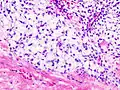

Imaging studies – including radiographs ("x-rays"), computerized tomography (CT), and magnetic resonance imaging (MRI) – are often used to make a presumptive diagnosis of chondrosarcoma.[9] However, a definitive diagnosis depends on the identification of malignant cancer cells producing cartilage in a biopsy specimen that has been examined by a pathologist. In a few cases, usually of highly anaplastic tumors, immunohistochemistry (IHC) is required.